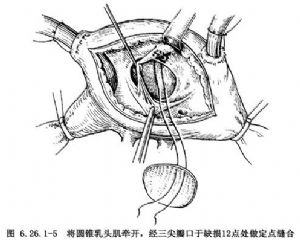

連續縫合補片修復法:由右房經三尖瓣口先於缺損12點部位,用4-0聚丙烯縫線做一單純縫合,補片修剪成略大於室間隔缺損(圖6.26.1-5),縫數針後拉緊縫線,將補片下送到位,繼續向頭端肌肉緣縫合(圖6.26.1-6左),牽拉縫線顯示下一步縫合區,抵達上方心室漏斗褶肌緣和三尖瓣環結合部後,縫線穿過三尖瓣前瓣基底部,自心室至心房側,隨後從心房回至心室側,穿過補片緣,收緊縫線(圖6.26.1-6右)。用另一頭縫線從缺缺損下緣往後繼續連續縫合(圖6.26.1-7左),到後下緣時縫線應離開缺損邊緣5mm,從間隔右室面進出針,切勿穿過間隔組織,以防損傷希氏束(圖6.26.1-7右)。兩針於相遇處結紮,閉合缺損。